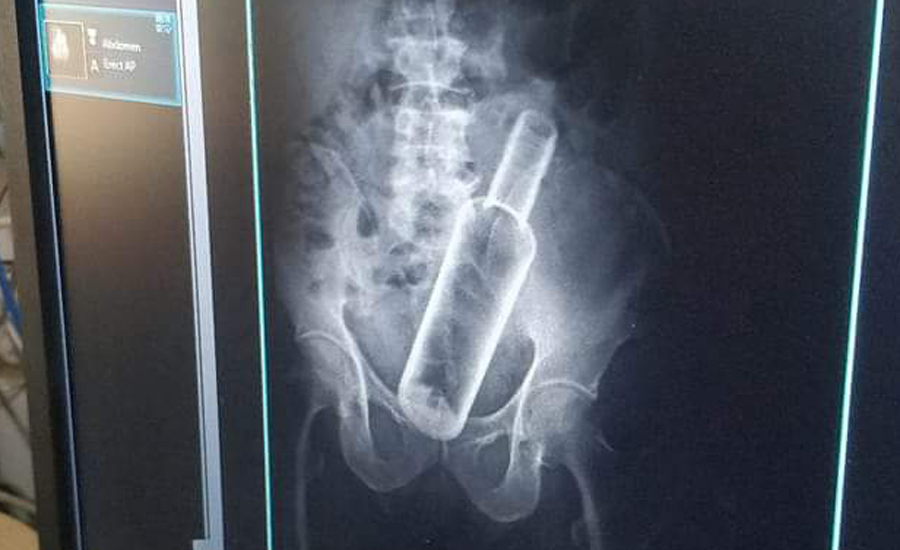

वृद्धको पेटमा बोतल भेटियो

सेती प्रादेशिक अस्पतालमा उपचार गर्न गएका एक वृद्धको पेटमा बोतल भेटिएको छ । धनगढीको फूलबारी बस्ने ६१ वर्षीय जमनसिंह रोकामगरको एक्सरे गर्दा पेटमा रक्सीको बोतल देखिएको अस्पतालले जनाएको छ ।

प्रादेशिक अस्पतालका सूचना अधिकारी मेखराज उपाध्यक्षले दिएको जानकारी अनुसार बिहीबार पेट दुखेपछि अस्पताल आएका रोकामगरको एक्सरे गर्ने क्रममा बोतल देखिएको हो ।

उनकाअनुसार केही दिनअघि मदिरा सेवन गर्ने क्रममा साथीले मलद्वारबाट बोतल पेटमा घुसाइदिएको बताएका छन् । उनको प्रादेशिक अस्पतालमा उपचार भइरहेको छ ।

यसअघि रौतहटका एक युवाको पेटमा पनि यस्तो बोतल भेटिएको थियो । चितवनको भरतपुरस्थित पुरानो मेडिकल कलेजका चिकित्सकले शल्यक्रिया गरी उनको पेटबाट बोतल निकालेका थिए ।